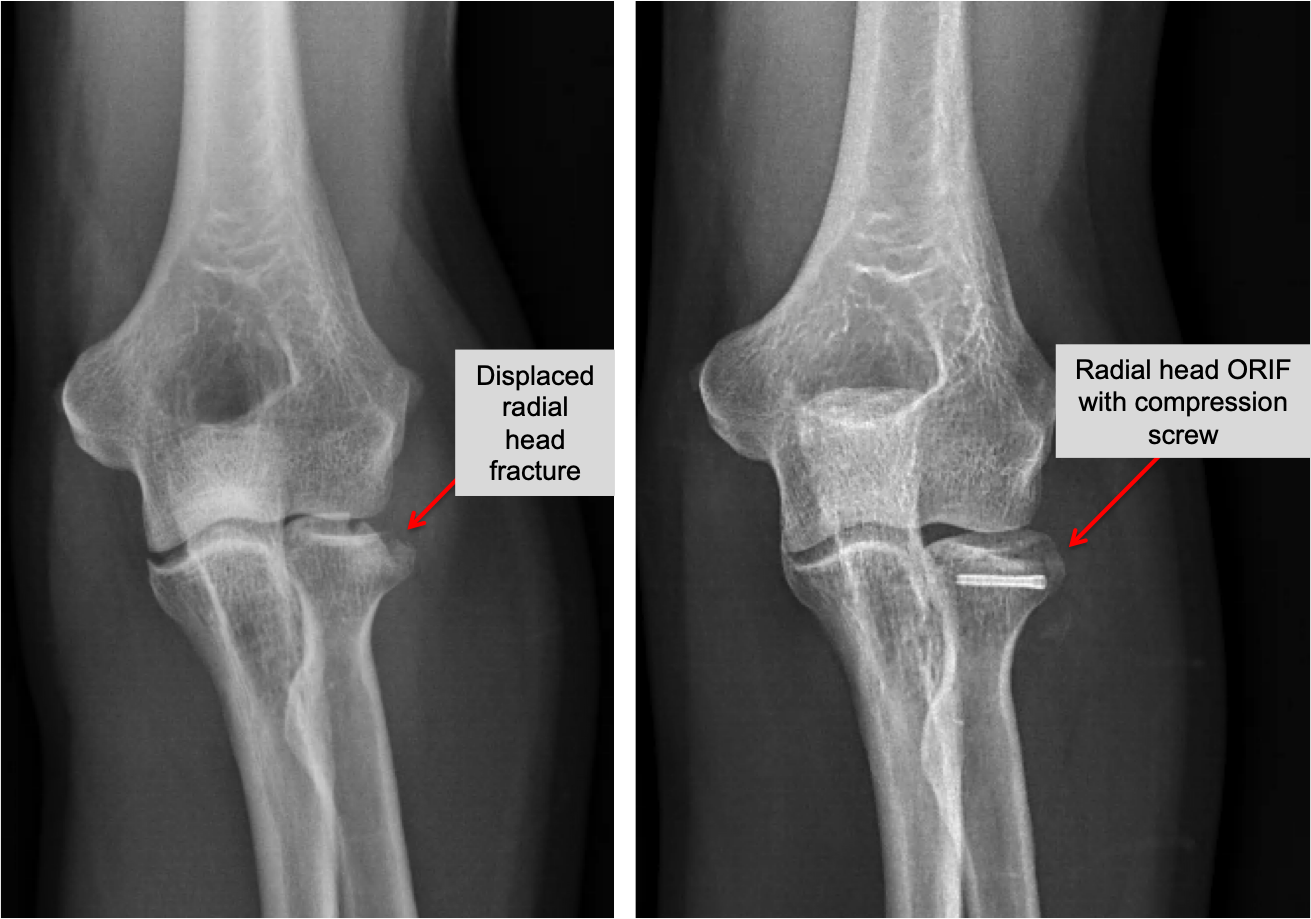

Radial Head Fracture — Joseph J. Schreiber, MD

From www.schreibermd.com